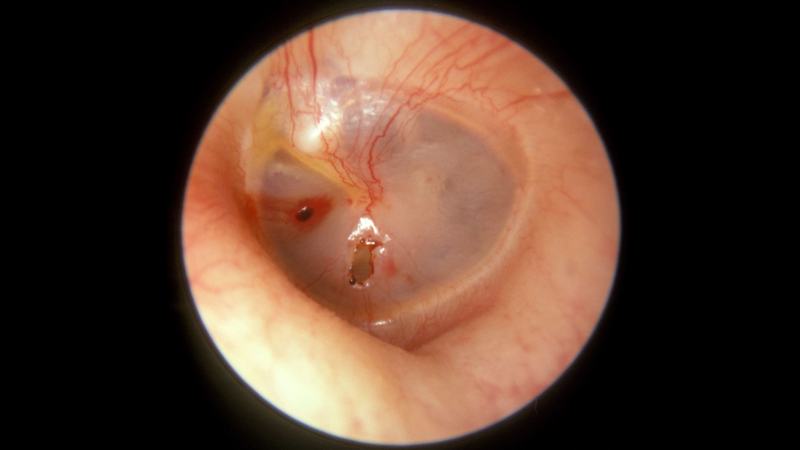

Đau tai là một trong những triệu chứng phổ biến nhất khiến bố mẹ đưa con mình đến gặp bác sĩ để tìm nguyên nhân và điều trị tình trạng này. Đau tai có thể là triệu chứng của nhiễm trùng tai hoặc là dấu hiệu của một tình trạng bệnh tiềm ẩn. Đau tai nguyên phát phổ biến hơn ở trẻ em, trong khi đau tai thứ phát phổ biến hơn ở người lớn. Phương pháp điều trị tùy thuộc vào nguyên nhân.

Đau tai được chia thành hai loại chính dựa trên nguyên nhân, bao gồm đau tai nguyên phát và đau tai thứ phát. Đau tai nguyên phát là triệu chứng xảy ra trực tiếp từ bệnh lý tai trong, tai giữa hoặc tai ngoài. Ví dụ như nhiễm trùng tai gây đau tai.

Đau tai thường do nhiễm trùng tai giữa, tích tụ ráy tai, viêm ống tai ngoài, hoặc chấn thương tai do áp suất thay đổi hoặc tiếp xúc với tiếng ồn lớn.